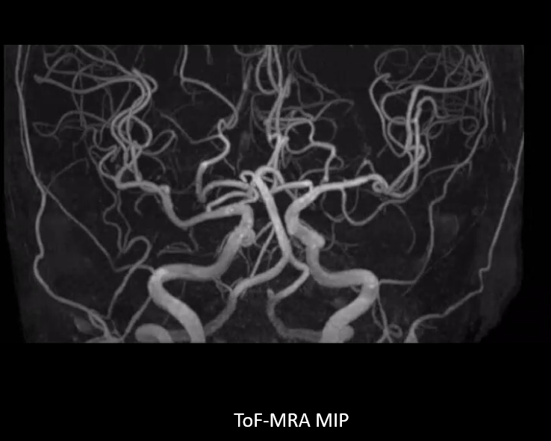

Lumina MRA画像

頭部単純MRI MRA画像